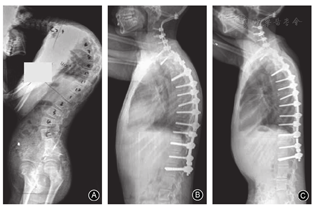

C7T1伸展性截骨组3例均合并单纯颈胸段后凸畸形,术前后凸Cobb角平均为17.0°±16.3°(4°~40°),末次随访改善至-13.3°±20.2°(-31°~15°),平均矫正率178.2%;术前CBVA平均为20.0°±4.5°(15°~26°),末次随访改善至4.7°±5.9°(0°~13°),平均矫正率76.5%;术前SVA平均为(6.9±4.0)cm(1.4~10.9 cm),末次随访改善至(3.5±1.8)cm(1.0~5.0 cm),平均矫正率49.3%(表1,图3)。

C7 PSO组共5例,4例合并侧后凸畸形、1例合并严重颈胸段侧凸畸形。4例合并侧后凸畸形患者术前后凸Cobb角平均为22.8°±10.5°(13°~40°),末次随访改善至-13.5°±10.0°(-28°~0°),平均矫正率159.2%;术前侧凸Cobb角平均为24.8°±12.7°(15°~46°),末次随访改善至5.0°±3.5°(0°~10°),平均矫正率79.8%(56.5%~100%);术前CBVA平均为60.5°±10.2°(50°~75°),末次随访改善至14.3°±8.6°(4°~25°),平均矫正率76.4%(51.9%~93.8%);术前SVA平均为(10.4±4.3)cm(3.6~15.4 cm),末次随访改善至(6.4±2.5)cm(2.7~9.8 cm),平均矫正率38.5%(7.5%~59.1%)。余1例合并严重颈胸段侧凸畸形患者,术前侧凸Cobb角为33°,末次随访改善至10°,改善率69.7%(表2,图4)。